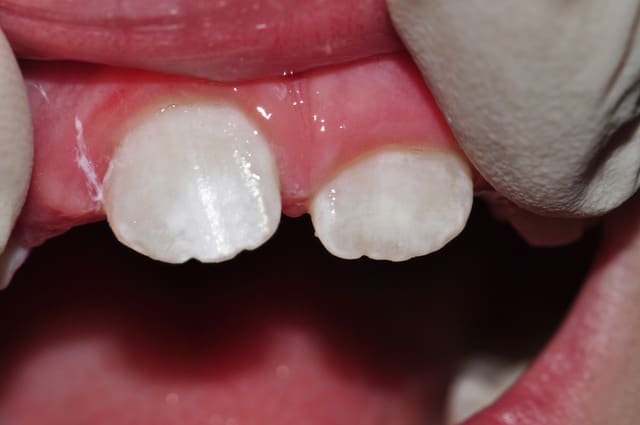

voila quelques traitements,modestes mais je suis encore jeune....

encore des radios,peut-etre assez moyen comme traitement...mais je vu pire...